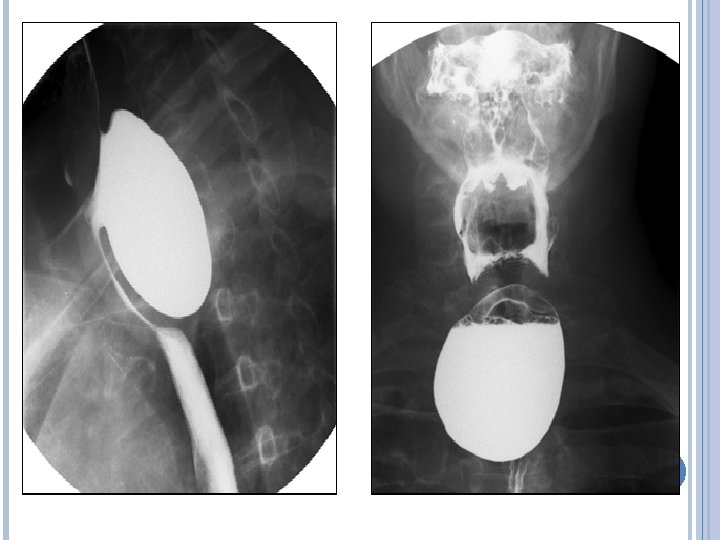

58 yaşında erkek, Birkaç aydır olan kilo kaybı ve yutma güçlüğü ile aile hekimliği polikliniğine başvurdu. Katı gıdaların boğazına saplanıyor gibi olduğunu belirtti. o İlgili bir tıbbi hastalık öyküsü ve anlamlı bir fizik muayene bulgusu yoktu. Ayaktan çekilen ösofagografisi şu şekildeydi:

TARTıŞMA Cevap E Zencker divertükülü Zenker divertikülü hipofaringeal mukozanın nadir posterior herniasyonudur. Bu durum alt faringeal constrictor ve Killian üçgeni olarak bilinen cricopharyngeus kasları arasındaki zayıf bir alan üzerinden gerçekleşir. Patogenezi belirsizdir , ancak durum üst ösofagial sfinkterin yetersiz açılması sonucu hipofaringeal basıncın artması ve protrüzyon geliştirmesi sonucu oluştuğu düşünülür.